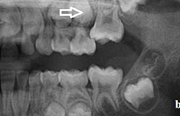

) Röntgenülesvõte. Ülemise esimese jäävmolaari lõikumine on takistatud 2. piimamolaari tõttu

Esimese jäävmolaari ektoopiline lõikumine